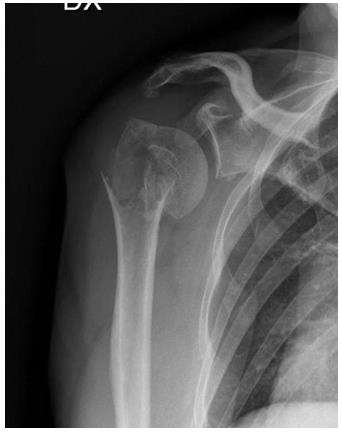

A 69-year-old woman came to ER of Poliambulanza of Brescia in October 2019. X-rays were obtained. Fracture involved proximal humerus of the right, dominant, upper arm. The fracture was 11C3.1 according to AO classification. At first, the fracture was treated with an external. fixation using a Galaxy EF in the first twenty-four hours. The EF was removed after one month because of the loss of reduction with displacement of the fracture. Physio- kinesitherapy was indicated but she was unable to underwent to treatment. She was lost at follow -up for several months due to COVID-19 pandemic and the social limitations that resulted. After 7 months, Xrays showed a dislocated nonunion of proximal humerus with necrosis of the head. She complained shoulder pain with passive elevation of 40° and scapular dyskinesia. In March 2021 she was listed for a reverse shoulder arthroplasty. During the surgery, Synovasure test and white blood cell count were performed: both tested negatives. A cemented trauma stem “Equinoxe” by Exactech number 8 mm was applied with a standard baseplate fixed with three screws of 26, 18, 18 mm. External rotators were reinserted, and range of motion (ROM) was good at three months follow-up.